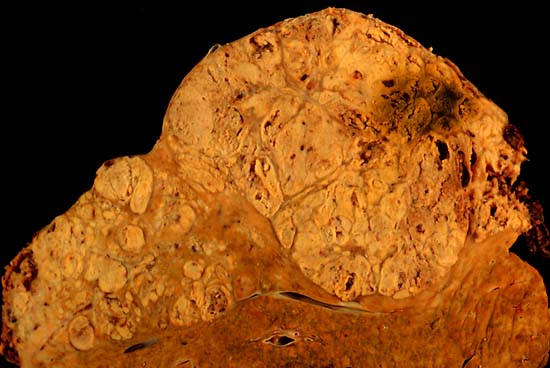

Cirrhosis

Cirrhosis is the last stage of liver damage and is marked by bands of fibrosis and hepatocyte regenerating nodules that disrupt the normal hepatic parenchyma.

Liver Metastasis

Compared to primary liver tumors, liver metastasis is more common.

Clinical diagnosis of liver metastasis may reveal a nodular free edge of the liver and hepatomegaly.

The most usual sources are liver metastasis are:

Radiology of liver metastasis usually show numerous nodules in the liver.